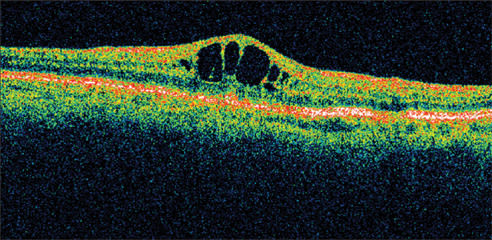

Figure 1. A 78-year-old woman complained of reduced visual acuity and contrast sensitivity OD 5 weeks after cataract surgery. Her presenting visual acuity was 20/40. Her IOP was 23 mm Hg, and retinal thickness was 478 μm on OCT.

Presenting visual acuity was 20/40. Her IOP was 23 mm Hg and retinal thickness was 478 μm on OCT (Figure 1). She was treated with nepafenac qid for 6 weeks and tapered over the ensuing 6 weeks. Her vision improved to 20/25 by 1 month with significant reduction in her retinal thickness (Figure 2). By 12 weeks, her visual acuity had improved to 20/20 with a retinal thickness of 216 μm and a normal foveal contour. This represents a reduction in retinal thickness of 262 μm from her pretreatment status (Figure 3). However, she continued to report a mild reduction in contrast sensitivity.